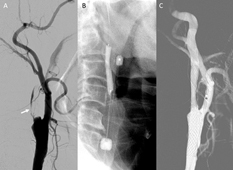

圖一 、(A) 內頸動脈近乎阻塞(箭號),置放遠端血管保護裝置有困難;(B) 可使用近側端囊球保護裝置,執行頸動脈支架置放;(C) 支架置放後,原先近乎阻塞的血管,恢復通暢